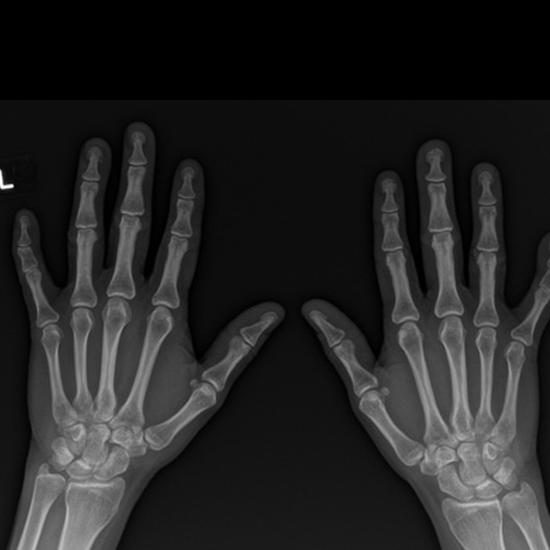

X-ray Both Hand AP & Oblique

What is an X-ray Both Hand AP & Oblique Views Test?

An X-ray of the hand uses a small quantity of radiation to safely and painlessly visualize the hand's bones and soft tissues (skin and muscles). Carpals, metacarpals, and phalanges are hand bones (bones of fingers).

Why is it done?

• To diagnose broken/fractured hand bones and track their healing.

• To identify infections, osteoporosis, bone abnormalities, and arthritis (inflammation of the joints).

What is the procedure for the both-hand AP and oblique views radiograph test?